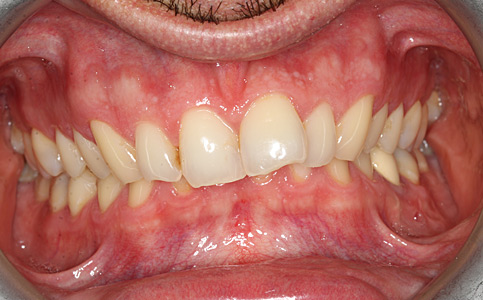

Pierwszym etapem była deprogramacja zgryzu i wyleczenie ubytków próchnicowych, następnie ustabilizowanie nowej pozycji szczęki względem żuchwy i poprawa estetyki zebów z tego powodu założone zostały korony pełnoceramiczne.